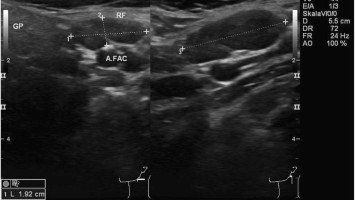

Wann sollten Sie an eine Riesenzellarteriitis denken?

Die Riesenzellarteriitis kann aufgrund ihrer unspezifischen Symptome leicht übersehen werden. Welche Warnsignale auf auf eine systemische Gefäßentzündung hindeuten und in der Hausarztpraxis erkannt werden sollten, fasst dieser Beitrag zusammen.

Titelbild Kongress Kompakt EULAR 2025/© Hintergrundbild: william87 / stock.adobe.com, Wunde wird mit Wundspray versorgt/© Ilja / Stock.adobe.com (Symbolbild mit Fotomodell), Kutane Arzneimittelreaktion/© Hötzenecker, W., Hautveränderungen an der rechten Wange/© M.V. Heppt, In Risikogebieten tragen circa 1–2 % der Zecken das FSME-Virus./© astendal / stock.adobe.com (Symbolbild mit Fotomodell), MRT-Aufnahmen der Kopfschwarte bei Riesenzellarteriitis/© Universitätsklinikum Würzburg, Fillerbehandlung im Gesicht eines Mannes/© Microgen / stock.adobe.com (Symbolbild mit Fotomodell), Neurofibromatose auf der Haut/© Alexander Schuh / Klinikum Fichtelgebirge, Wespen auf Stein/© merlion / Getty Images / iStock (Symbolbild), Eine Person raucht eine E-Zigarette/© vchalup / stock.adobe.com (Symbolbild mit Fotomodell), Mund mit herausgestreckter Zunge: Medikamenteninduzierte Xerostomie mit extrem trockener Mundschleimhaut/© F. Halling | Die junge Zahnmedizin (16)·3:26-31, Aknenarben/© Hautwerk, Konfokale optische Kohärenztomographie mit Line-Field-Technologie/© Deußing, M. et al. / all rights reserved Springer Medizin Verlag GmbH, Ex vivo konfokales Laserscanmikroskopiebild eines Morbus Bowen/© Grunewald S et al. / all rights reserved Springer Medizin Verlag GmbH, Zwei Injektionspens mit Semaglutid/© Kassandra / Stock.adobe.com, Immuncheckpointinhibitoren binden an Krebszelloberflächenproteine /© Juan Gärtner / stock.adobe.com, Morbus Castleman: Sonographie eines Lymphknotens/© Springer Medizin, Person kratzt sich am Arm/© 9nong / stock.adobe.com (Symbolbild mit Fotomodell), Arzt tastet Bein ab/© Stratocaster / Stock.adobe.com (Symbolbild mit Fotomodellen), Hämorrhagisches Erysipel am Unterschenkel/© Sunderkötter C et al. / all rights reserved Springer Medizin Verlag GmbH, Piks in Oberarm/© stalnyk / stock.adobe.com, Gewitter mit Blitzschlag/© solarseven / Getty images / iStock, Behandlung eines diabetischen Druckulkus/© Alexander Schuh, Eine Person, die sich juckt und kratzt/© Maria Fuchs / stock.adobe.com (Symbolbild mit Fotomodell), Die Leitlinien für Ärztinnen und Ärzte, Herpes Zoster am Rücken/© Mumemories / Getty Images / iStock (Symbolbild mit Fotomodell), Mann erhält einen CT-Scan /© Mark Kostich / stock.adobe.com (Symbolbild mit Fotomodell), DGIM Podcast-Reihe - Frailty/© (M) David L / peopleimages.com / Stock.adobe.com (Symbolbild mit Fotomodell)